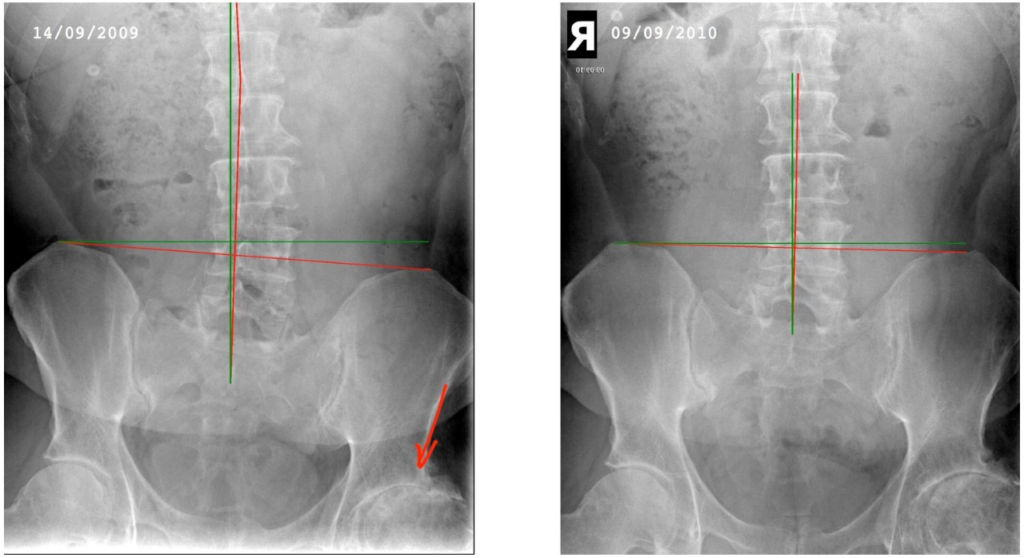

These X-Rays were taken almost 1 year apart. In the X-Ray on the left which was taken as this member was accepted into care, can you notice the profound pelvic tilt? If you look at the left hip joint (red arrow) you can see the re-modelling that this has caused. A year later we can see a remarkable improvement in the pelvic alignment, but something less obvious has improved too.

Look at the enlarged views of the hips below. Observe how after 1 year the cartilage has re-grown, you can see this by the bigger gap in the joint. When you look at an X-Ray the dark gaps between bones are made by the joint cartilage. No Gap = very little cartilage, but bigger gap = healthier joint = arthritis reversing!